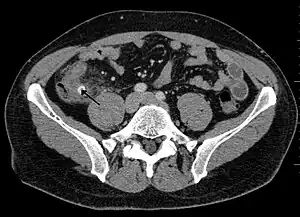

Computed tomography

Where it is readily available, computed tomography (CT) has become frequently used, especially in people whose diagnosis is not obvious on history and physical examination. Although some concerns about interpretation are identified, a 2019 Cochrane review found that sensitivity and specificity of CT for the diagnosis of acute appendicitis in adults was high.[59] Concerns about radiation tend to limit use of CT in pregnant women and children, especially with the increasingly widespread usage of MRI.[60][61]

The accurate diagnosis of appendicitis is multi-tiered, with the size of the appendix having the strongest positive predictive value, while indirect features can either increase or decrease sensitivity and specificity. A size of over 6 mm is both 95% sensitive and specific for appendicitis.[62]

However, because the appendix can be filled with fecal material, causing intraluminal distention, this criterion has shown limited utility in more recent meta-analyses.[63] This is as opposed to ultrasound, in which the wall of the appendix can be more easily distinguished from intraluminal feces. In such scenarios, ancillary features such as increased wall enhancement as compared to adjacent bowel and inflammation of the surrounding fat, or fat stranding, can be supportive of the diagnosis. However, their absence does not preclude it. In severe cases with perforation, an adjacent phlegmon or abscess can be seen. Dense fluid layering in the pelvis can also result, related to either pus or enteric spillage. When patients are thin or younger, the relative absence of fat can make the appendix and surrounding fat stranding difficult to see.[63]